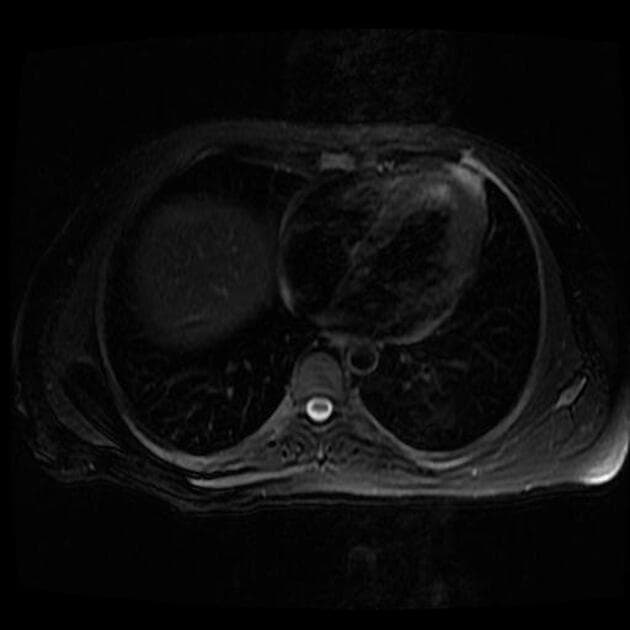

- Tăng tín hiệu trên hình ảnh T2/FLAIR kèm hạn chế khuếch tán rõ rệt, đối xứng hai bên, ảnh hưởng đến chất trắng, đặc biệt vùng trên lều (bán nguyệt phóng xạ, trung tâm bán nguyệt), cuống tiểu não giữa, và chi sau của bao trong, lan xuống đến cuống não.

- Các sợi U dưới vỏ được bảo tồn (nhận thấy rõ nhất trên FLAIR và T2).

Hình ảnh tổn thương đặc trưng bởi tính đối xứng rõ rệt, khu trú ở những vùng chất trắng cụ thể và bảo tồn các sợi U dưới vỏ (subcortical U-fibers).

Trong bối cảnh hóa trị, những thay đổi hình ảnh này gần như chắc chắn biểu hiện cho bệnh lý chất trắng do độc chất (toxic leukoencephalopathy), nguyên nhân có khả năng nhất là do 5-fluorouracil.